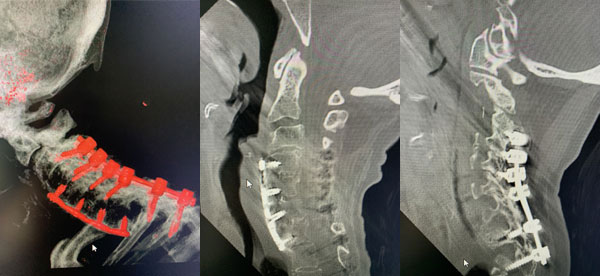

Figure 1: Sagittal T2 MRI of the cervical spine demonstrates severe spinal cord compression at C2-3 above prior to instrumented decompression and fusion.

Figures 2a, b, c: Preoperative sagittal CT scans of the cervical spine demonstrating preoperative instrumentation. Note degenerative changes and anteriolisthesis of C2 and C3.